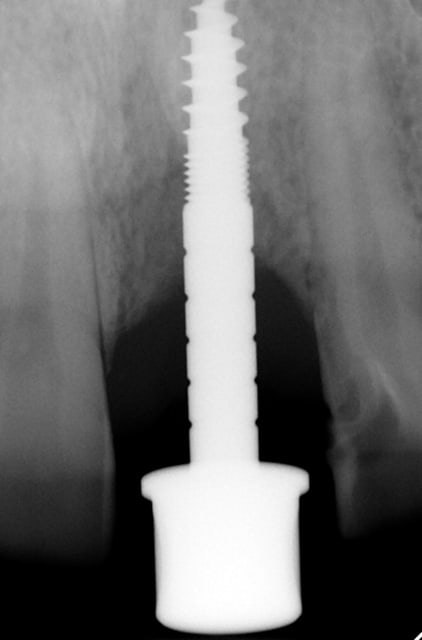

J'ai de tout en boutique..jeune homme 25 ans accident de piscine choc sur la bordure ( fêlure existante..fistule), extraction le jour même, temporisation 4 mois (avec un bout de trombone) Monobloc 16mm 60N, prep cap zircone droit 2/2 provisoire ion, temporisation 3 mois ceramo ceram..

Au contraire..si tu regarde attentivement les radios tu veras qu'en quelques mois il y a une néoformation osseuse autour des micros spires. On voit un manque le jour de la pose et plus d'os avec la Procera. Volontairement j'ai pas plus enfoncé l'implant ..Si j'avais ouvert j'aurai bousillé tout le potentiel cicatriciel..Charon l'a démontré depuis longtemps en paro. Aux patient je leur explique que "Ouvrir c'est comme tondre le gazon avec un motoculteur" .

Donc il y maintien et renfort du parodonte.